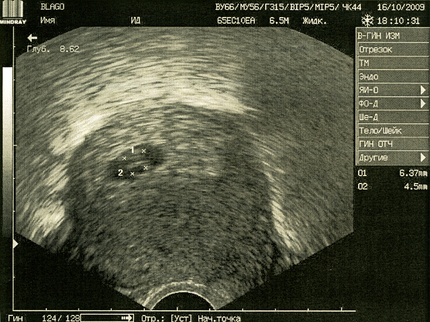

Узи после эко день

Узи после эко день 144 фото